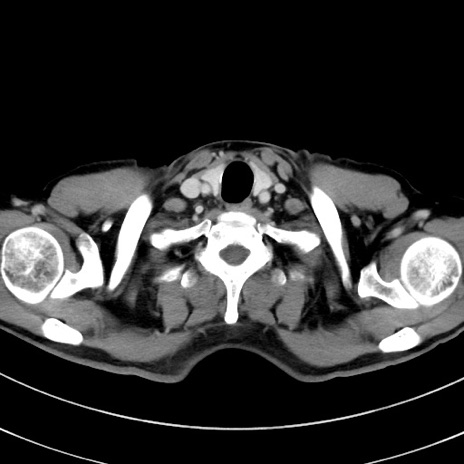

症例8(横断像)

【症例】 60歳代男性

【主訴】 黒色吐物

【現病歴】 4日前から嘔気自覚、2日前の朝食後にも嘔気あり、自分で手で嘔吐反射起こし嘔吐したところ血が混ざっていたため受診。

【既往歴】 5年前汎発性腹膜炎を伴う急性虫垂炎で手術、高血圧、前立腺肥大症、高脂血症

【身体所見】 腹部正中に手術癩痕あり 腹部平坦・軟圧痛なし膨満感あり

【データ】WBC 8400、CRP 4.54